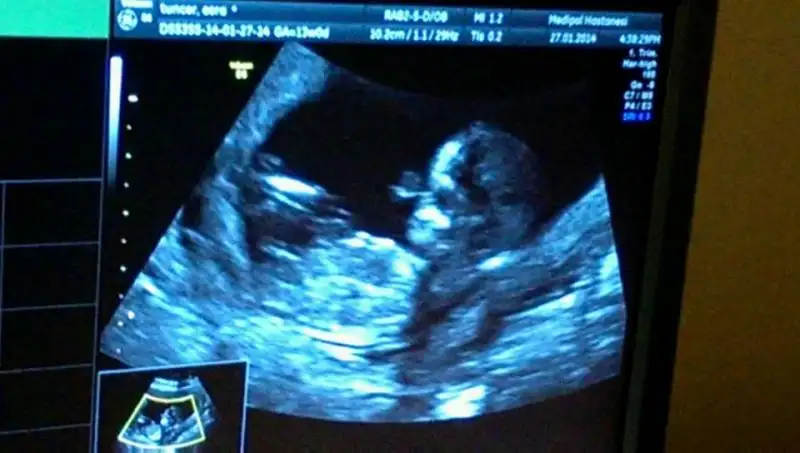

Günaydın arkadaşlar dün ikili testim çok güzel geçti minişimin her şeyi gayet normalmiş boyumuz 66mm olmuş çok uzamış :)) hata annesine nanik bile yaptı miniğim :) sabahtan beri bana verdikleri cd izliyorum günaydın minişime deyip :)) Eki Görüntüle 952594

Nub teorisinde gordum bebisini canim, cinsiyet tahmini bile yapmislar :) cok sevindim darisi basimiza insallahGünaydın arkadaşlar dün ikili testim çok güzel geçti minişimin her şeyi gayet normalmiş boyumuz 66mm olmuş çok uzamış :)) hata annesine nanik bile yaptı miniğim :) sabahtan beri bana verdikleri cd izliyorum günaydın minişime deyip :)) Eki Görüntüle 952594

cinsiyeti için hiç birşey söylemedi 2 hafta daha bekleyeceğiz dedi ben 2 haftadaha nasıl bekleyeceğim bilmiyorum :)) ama salı günü kendi dr gideceğim sonuçlarımı göstermek için belki o söyler :)) ense kalınlığı 1,2mm çıktı benimde her şeyi çok normla dedi böbrekleri mide bağırsaklar burun kemiği herşey yerli yerine oturmuş dedi :)) bunda çok sevindim rabbime hep dua ediyorum hepimizin minişlerini sağlık versin